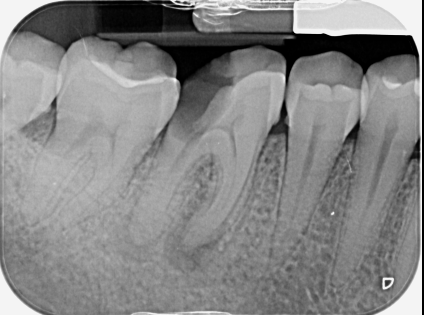

Il trattamento endodontico (devitalizzazione) consiste nel rimuovere la polpa dentaria o piu comunemente il nervo contenuto all’interno del dente e nelle sue radici, che sia infetto o infiammato.

La causa piu comune è di gran lunga la carie dentaria che, non essendo stata intercettata in uno stato iniziale, ha progredito fino a raggiungere il nervo. Una volta intaccata, la polpa va incotro ad un processo infiammatorio acuto denominato pulpite, o necrosi con conseguente ascesso.